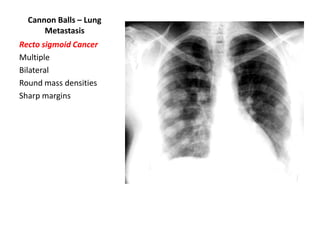

Cannon Balls – Lung

Metastasis

Recto sigmoid Cancer

Multiple

Bilateral

Round mass densities

Sharp margins